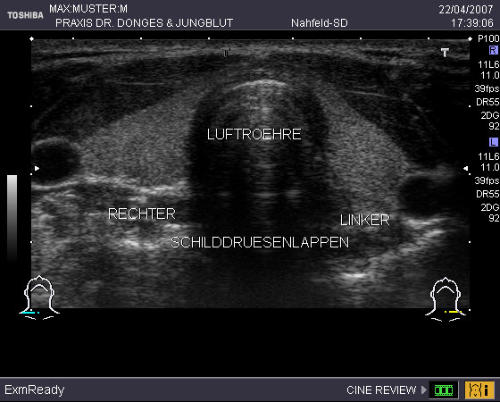

Schilddrüse Ihre Schilddrüse bildet Hormone, die für den Stoffwechsel von großer Bedeutung sind. Sie benötigt hierfür eine genügende Jodzufuhr mit dem Trinkwasser und der Nahrung. Trotz aller Anstrengungen ist die Jodversorgung in Deutschland noch nicht ausreichend, so dass aktuell immer noch jeder dritte Erwachsene (!) eine vergrößerte oder knotig veränderte Schilddrüse hat. Durch Früherkennung und Behandlung lassen sich spätere Operationen vermeiden. Deshalb bieten wir Ihnen einen Vorsorgetest an, der neben dem Abtasten eine Ultraschall-untersuchung der Schilddrüse und einen Laborwert (TSH) beinhaltet. Hiermit können wir das Organ exakt in Größe, Knotenbildung und Funktion beurteilen. Der Vorsorgetest ist keine Krankenkassenleistung.

Schilddrüse Ihre Schilddrüse bildet Hormone, die für den Stoffwechsel von großer Bedeutung sind. Sie benötigt hierfür eine genügende Jodzufuhr mit dem Trinkwasser und der Nahrung. Trotz aller Anstrengungen ist die Jodversorgung in Deutschland noch nicht ausreichend, so dass aktuell immer noch jeder dritte Erwachsene (!) eine vergrößerte oder knotig veränderte Schilddrüse hat. Durch Früherkennung und Behandlung lassen sich spätere Operationen vermeiden. Deshalb bieten wir Ihnen einen Vorsorgetest an, der neben dem Abtasten eine Ultraschall- untersuchung der Schilddrüse und einen Laborwert (TSH) beinhaltet. Hiermit können wir das Organ exakt in Größe, Knotenbildung und Funktion beurteilen. Der Vorsorgetest ist keine Krankenkassenleistung.